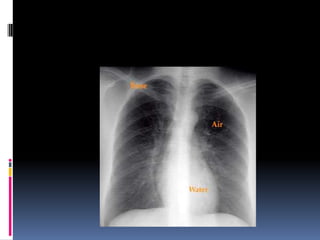

Different tissues in body absorb X-rays at

different extents:

• Bone- high absorption (white)

• Tissue- somewhere in the middle absorption (grey)

• Air- low absorption (black)

Different tissues inbody absorb X-rays at different extents: • Bone- high absorption (white) • Tissue- somewhere in the middle absorption (grey) • Air- low absorption (black)